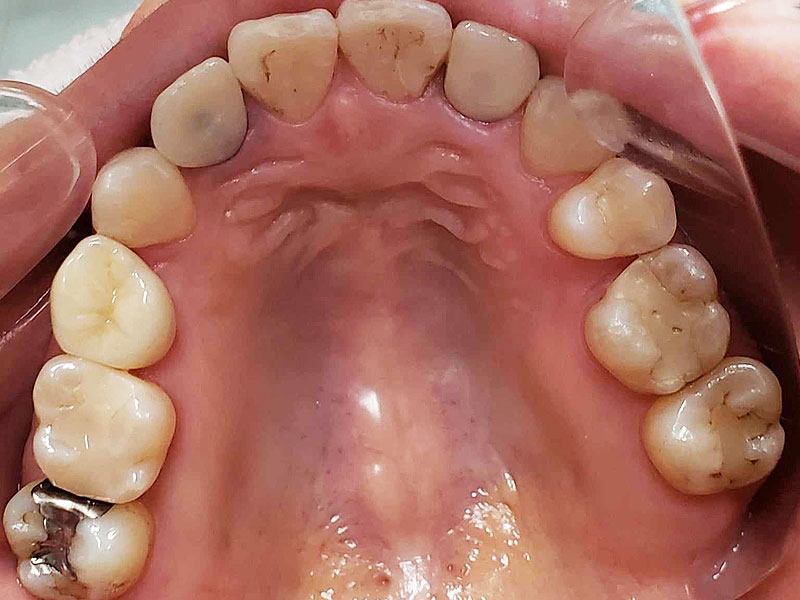

術前

• 初診:2006年、2014年―矯正治療を含めた一口腔単位の治療開始、治療当時、30代女性、非喫煙者

• 主訴:できれば歯並びを良くし歯を白くしたい。

• 治療方針:親知らず3本抜歯、上下小臼歯4本抜歯、矯正用インプラント使用のワイヤー矯正、修復処置、保定(上マウスピース、下ワイヤー)、メンテナンス